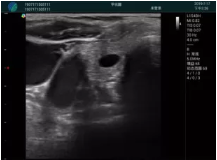

可視化甲狀腺穿刺引導(dǎo)

頸動脈血流充盈飽滿,無外溢

肝內(nèi)血管顯示清晰,血流敏感無外溢

甲狀腺囊性結(jié)節(jié),囊壁鈣化,透聲好

甲狀腺囊性占位

2001年美國健康護理研究和質(zhì)量監(jiān)督局(AHRQ)批準了一項關(guān)于提高患者安全性的報告,建議:在頸內(nèi)靜脈中心置管術(shù)時使用超聲引導(dǎo)。此后超聲引導(dǎo)穿刺被用于幾乎所有的急診穿刺操作,尤其是血管穿刺。

便攜超聲在急診穿刺中的應(yīng)用: